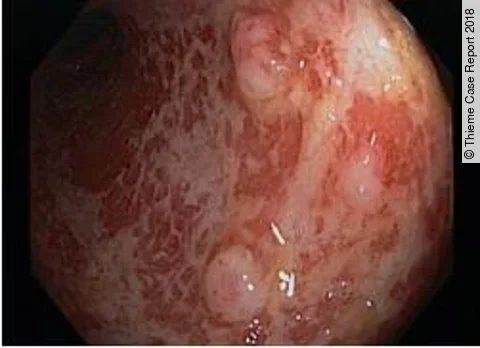

Endoskopisches LehrvideoPolyp im Divertikel

Unser neues Endoskopie-Video zeigt einen offensichtlichen Befund, der aber auch leicht zu übersehen ist. Welcher das ist und welche Methode zur Behandlung angewandt wurde, präsentiert PD Dr. Jochen Weigt vom Uniklinikum Magdeburg.